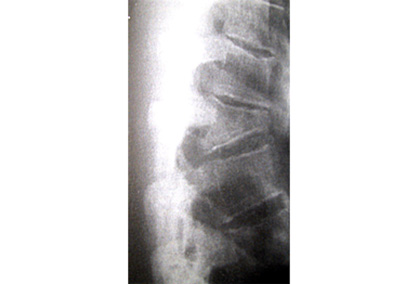

- plain x-rays